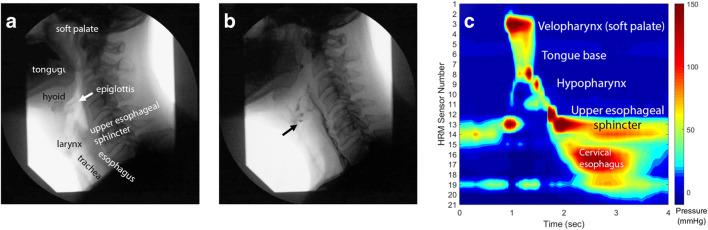

There have been several improvements in quantitative descriptions of swallowing physiology using standard and new evaluation techniques. These descriptions have been correlated with lesion locations, and several factors can predict development of post-stroke dysphagia and its sequelae. Novel treatment paradigms have leveraged post-stroke neuroplastic improvements using neurostimulation and biofeedback techniques. Despite recent findings, the field is limited by lack of standardization and unanswered questions on rehabilitation variables. Our improved understanding of post-stroke dysphagia will enhance our ability to prevent, identify, and treat it. Future work should be grounded in swallowing physiology and continue refining treatments, particularly in the acute stage.